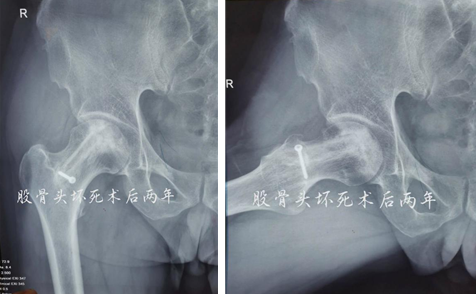

术后两年

术后12个月和24个月,患者来院复查,影像片子显示患者右侧股骨头髋臼平整光滑,股骨头圆润光滑,股骨头内骨小梁密度均匀,已恢复至正常股骨头状态,几乎与正常人股骨头无异。患者随访时说:“来医院之前,我独立行走都困难,短短几米的距离,我可能要花费三四分钟才能走完。手术之后,我不仅可以健步如飞,还能做下蹲等动作,也不必担心重体力劳动导致股骨头无法承受的问题,这个手术真的是太好了,不仅救了我,也救了我一家人……”